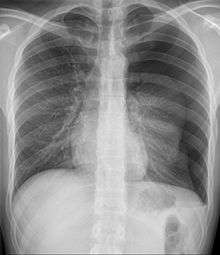

Since most causes of pediatric and adolescent chest pain are not considered life-threatening, parents and their children are often reassured that in the majority of cases, the cause of the pain can be determined. If the child or adolescent appears to have some dehydration, and intravenous line along with administration of saline is done. The clinician may or may not decide to perform diagnostic testing . This is especially true if the child or adolescent has symptoms of chronic pain. If an obvious cause of the chest pain is not readily apparent, testing may begin with an x-rayand an electrocardiogram . This helps the clinician to determine whether or not the cause of pain is related to pulmonary or cardiac causes.[4]